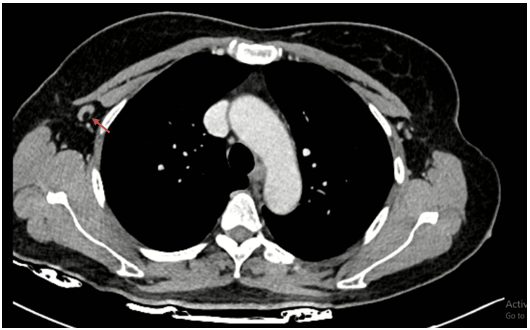

Chụp cắt lớp vi tính lồng ngực có tiêm thuốc: Hình ảnh nốt đặc nhỏ thùy dưới phổi phải. Dải xẹp thùy giữa phổi phải. Nốt ngấm thuốc 1/4 dưới ngoài vú phải đường kính 20mm, bờ ranh giới không rõ, ngấm thuốc sau tiêm.

Hình 3:

Hình ảnh nốt ngấm thuốc 1/4 dưới ngoài vú phải đường kính 20mm, bờ ranh giới không rõ, ngấm thuốc sau tiêm (mũi tên đỏ).